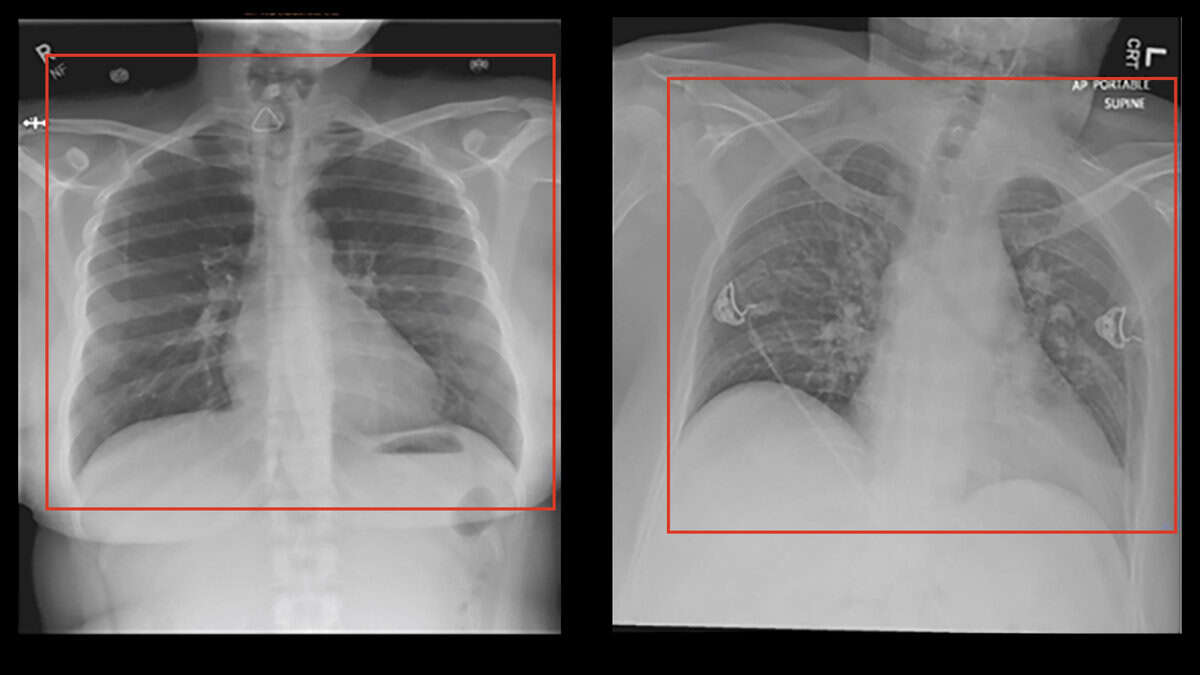

Back in May 2020, with Covid-19 everywhere on the rise and scarce resources to diagnose it, there was tremendous pressure for quick diagnostic or screening tests, which AI applications were hastily developed to satisfy. Several Machine Learning algorithms were trained to recognise signs of covid in chest radiographs and CT scans, scoring high in internal metrics of performance. On the basis of these, some advocated the fast implementation of mass scale CT-scans to air travelers as a quick and efficient screening. Luckily the dystopian travel process described in the image was never implemented. Only later was it actually shown that none of these algorithms was any good, despite promising internal precision. A paper in Nature Machine Intelligence (Roberts et al 2021) concluded that not one of the 62 models reviewed was any good in actual clinical application, with most of the flaws being identified in the process that was used to train the algorithms, which was plagued by deficiencies and bias. In one case for example the positive covid patients used to train the model were all bedridden, while the healthy controls were standing. The algorithm showed high internal precision in detecting Covid-19 on the basis of chest radiographs, but failed to perform in actual clinical setup. It was then realised that the algorithm had learned to identify if the patient was in lying or standing position, rather than the Covid-19 status.

Spot the ...x differences..!

Bedridden patients were frequently x-rayed with portable devices and under different settings. The patients' position was not as symmetrical as the standing patients, with slight rotations and irregular placement in the frame. The radiographs were also sometimes marked with text indicating portable device and subpine position. In a very cool demonstration of street-smart intelligence, the machine learned how to pass the exam, but never really learned the content...! This can be a typical case of what we call "overfit" algorithms, where the machine learning has evaluated too specific patterns in the training sample, including irrelevant ones and noise, thus becomes increasingly unable to detect relevant patterns in new samples, although highly successful in the training samples.